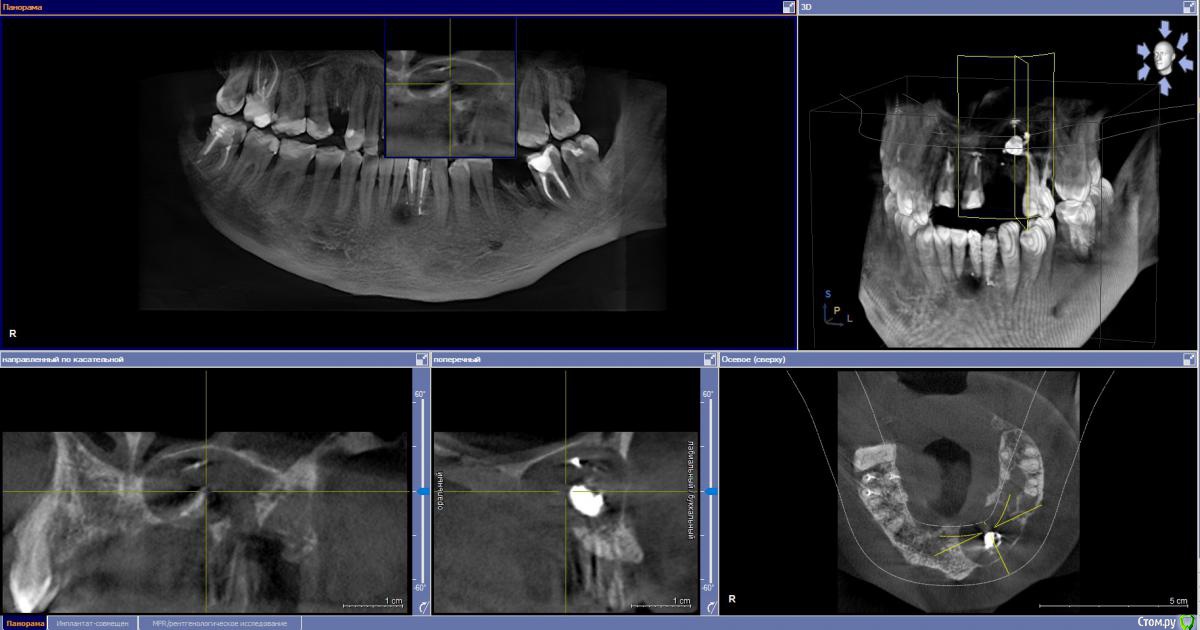

Ponchik Опубликовано 17 ноября, 2015 Поделиться Опубликовано 17 ноября, 2015 (изменено) Пациента ничего не беспокоит. В анамнезе травма 2 сегмента 7 лет назад. Пришел с целью протезирования. Ортопед удалили 22 и направил кисту убрать. Сделали прицельный.Потом захотелось КТ. КТ вышло не очень, но общее представление составить можно. Появились вопросы. На сколько велика вероятность встречи с синусом? Стоит делать амбулаторно? Опыт до этого - цистэктомии в пределах 1-2 зубов. Думаю куда направить. Изменено 17 ноября, 2015 пользователем Ponchik Ссылка на комментарий